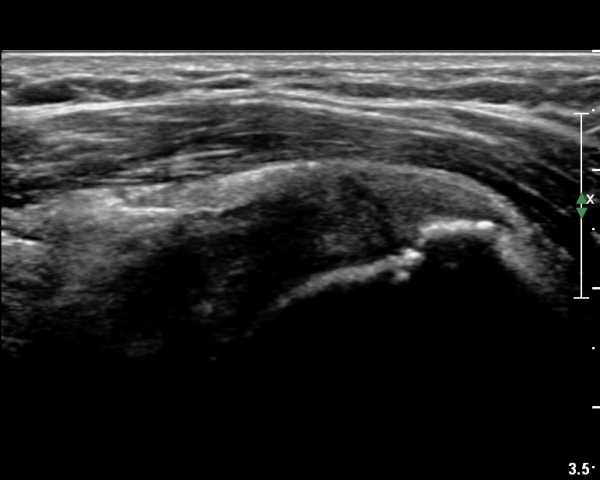

ÃÊÀ½ÆÄ °Ë»ç

´ë°áÀý°ú °ßºÀÇϺο¡ ¹æ»ç¼± Åõ°ú¼º °¨¼Ò(sclerosis)°¡ °üÂûµÈ´Ù(÷ºÎÆÄÀÏ).